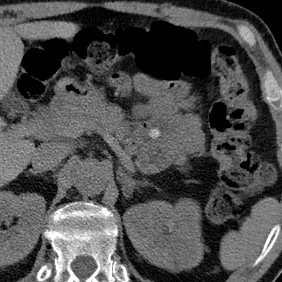

Intrahepatic biliary calculi

Gopal Punjabi

March 19, 2018